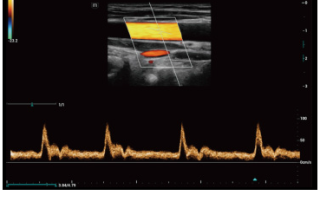

Mindray Ultrasound Consona N9